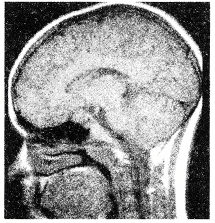

- 单项选择题关于星形细胞瘤(如图所示)的描述不正确的是

A、可分为纤维型、原浆型、肥胖细胞型

B、可不限于一个脑叶

C、肿瘤多呈浸润性生长

D、主要位于灰质内

E、实性者无明显边界